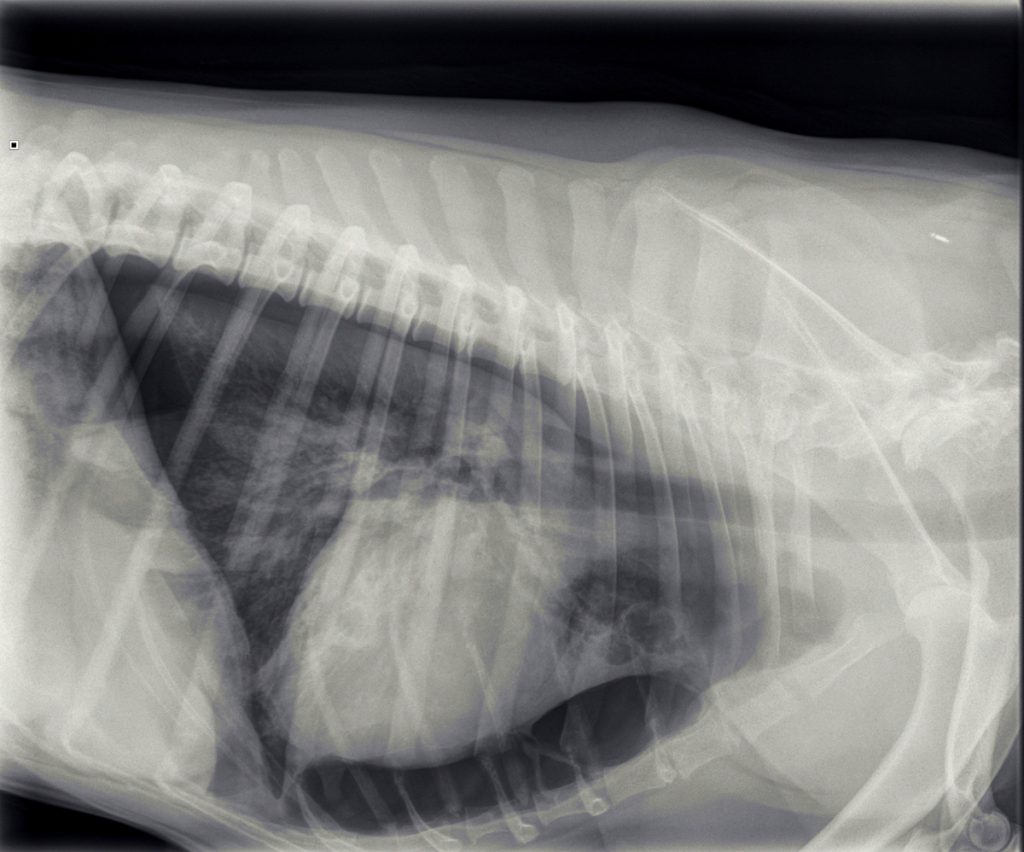

In overleg met de eigenaar van Jessie is besloten om röntgenfoto’s te maken.

Hierop was te zien dat er sprake was van een beiderzijdse klaplong. Dit betekent dat Jessie’s longen vrijwel geen lucht meer bevatten en ingeklapt in de borstholte lagen met lucht eromheen. Normaal hoort er geen lucht tussen de longen en de borstwand aanwezig te zijn.

In de loop van de volgende dag werd de hoeveelheid lucht, die we konden afzuigen, steeds minder en ging het steeds beter met Jessie. Omdat het voor Jessie prettiger was, ging Jessie het einde van de dag naar huis. Jessie was enorm blij om haar baasje te zien en was eigenlijk wat te wild in de begroeting. Na 1,5 uur belde de eigenaar ons op, dat het niet goed ging, dus Jessie moest gelijk terugkomen. Jessie was weer erg kortademig. Dit was verbazend, gezien hoe goed het eigenlijk ging. We hebben nieuwe röntgenfoto’s gemaakt en zagen weer veel lucht. Mogelijk was er toch weer iets gaan lekken door de eerdere activiteit.